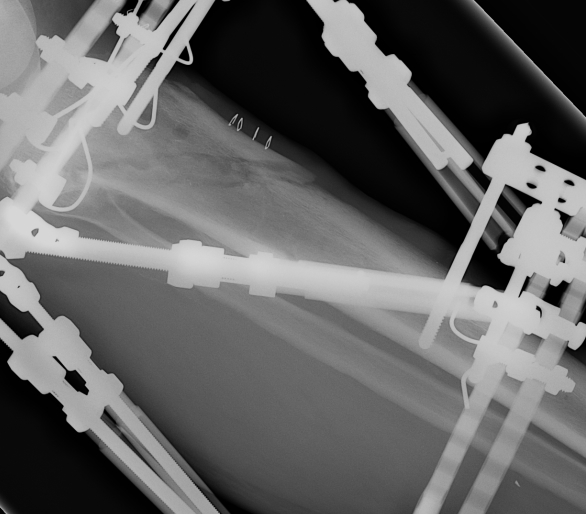

Xray of entire tibia and rings

- xray centred on proximal tab of proximal ring

- AP and Lateral all in one film

- the entire diameter of the rings must be on the film

Measure AP and Lateral View Axial Frame Offset

The tibia is not in the centre of the rings

- usually anterior

- need to tell computer where the proximal fragment is in reference to the rings